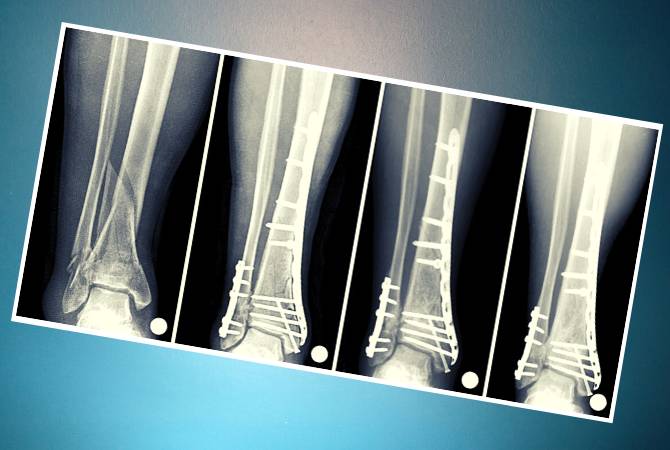

Остеосинтез проводится при сложных переломах голени. В процессе операции сломанные кости в правильном положении надежно фиксируются при помощи пластин, стержней, спиц, проволоки и винтов. Приспособления выполнены из нержавеющей стали, хромо никелевых и титановых сплавов. А также это могут быть искусственные материалы, рассасывающиеся в теле.

Операцию остеосинтеза выполняют через 2–3 дня после травмы. При тяжелом общем состоянии пациента, через две три недели. Успех манипуляции зависит от сохранности костных отломков, их точного сопоставления. С минимальным повреждением мягких тканей и сохранением кровоснабжения в месте перелома. Правильно спланированным восстановительным периодом.

Есть несколько способов фиксации отломков. Репозиционный предусматривает удержание костей в нужном положении без последующей нагрузки на конечность. После операции на ногу накладывают гипсовую повязку или лонгету. Функционально-стабильный метод оказывает хороший укрепляющий эффект и возможность двигать конечностью. В первый период минимальная нагрузка, затем постепенно увеличивается до полной.